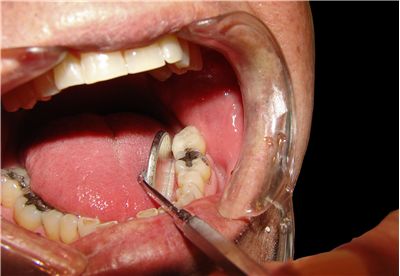

Dental caries , tooth decay or a cavity, is an infection caused by bacteria which ferments food debris and produces acid which, in turn, causes demineralization and destruction of the hard tissues of the teeth (enamel, dentin and cementum). It is one of the most common diseases throughout the world and history. Study of dental caries is called cariology.